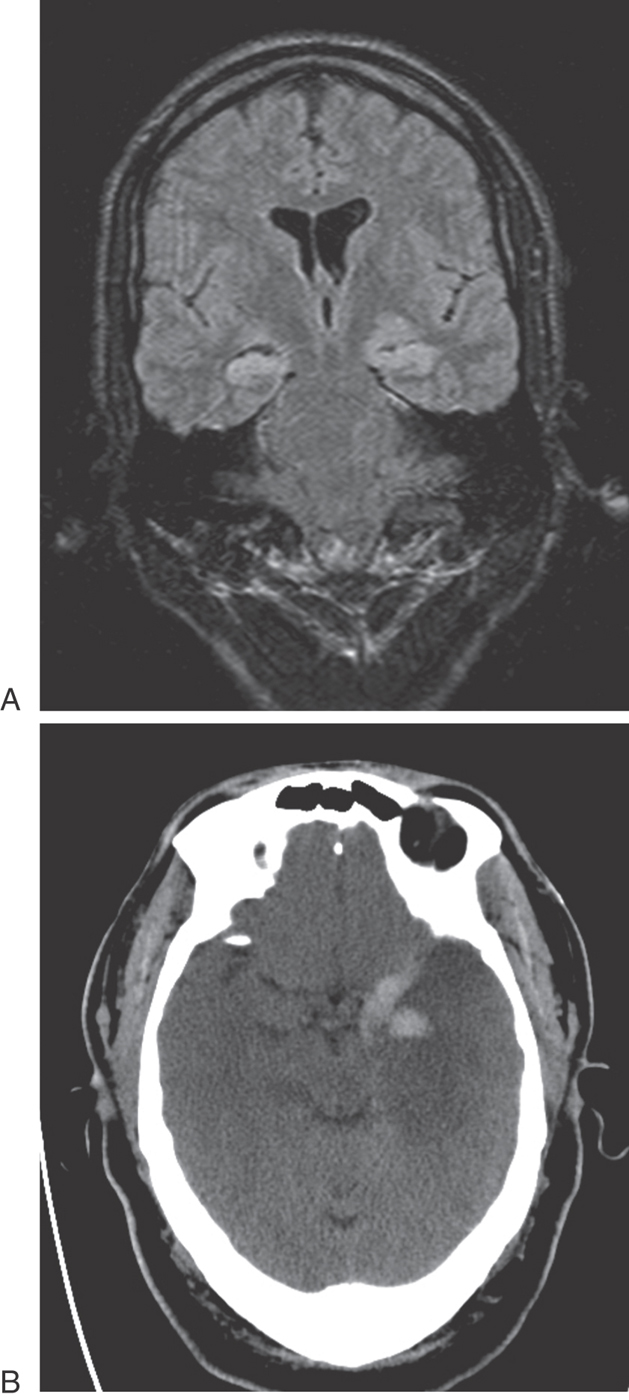

Defects in memory can also result from prolonged thiamine deficiency. This B vitamin deficiency typically seen in the context of chronic alcoholism, cancer cachexia, or any prolonged state of malnutrition causes a characteristic pattern of degeneration in the brain (Fig. 31-7). Typically, the mammillary bodies are involved, with some incursion into the dorsomedial nucleus of the thalamus and the columns of the fornix. There is also a loss of neurons in the hippocampal formation (Fig. 31-7). These patients with Korsakoff psychosis (alcoholic dementia) show a defect in short-term memory and consequently also in long-term memory for events occurring since the onset of the disease. They may appear demented, and they are prone to confabulation; that is, they tend to string together fragments of memory from several different events to form a synthetic “memory” of an event that never occurred (Table 31-2). Korsakoff psychosis is irreversible. Thiamine deficiency may also be manifested more acutely as a triad of eye movement abnormalities, ataxia, and confusion known as Wernicke encephalopathy, which is reversible with thiamine replacement. Table 31-2 contrasts the acute and chronic neurologic consequences of thiamine deficiency. In severe cases, patients may present with the Wernicke triad accompanied by profound memory loss; this condition is called Wernicke-Korsakoff syndrome.

Figure 31-7. Axial computed tomography scan showing severe atrophy of temporal and frontal lobes as well as prominent cerebellar folia (also a sign of atrophy) in a patient with alcohol dementia. Also note the enlarged temporal horns of the lateral ventricles (arrows).

Limbic structures are very sensitive to seizure activity. Damage to the mesial temporal lobes, mesial temporal sclerosis (Fig. 31-10A), is the most common cause of complex partial seizures. This type of seizure starts in a specific area of the brain, resulting in a wide range of physical and emotional behaviors with alteration of consciousness. Partial seizures are often associated with a warning or an aura. For example, seizures that start in the area of the uncus may be associated with olfactory or gustatory hallucinations referred to as uncinate fits. These sensations are explainable given the functions of the amygdala and the destinations of the olfactory-gustatory fiber systems. Seizures starting in other areas of the limbic system may be associated with visual illusions, sensations of impending doom, déjà vu (unfamiliar seems familiar), jamais vu (familiar seems unfamiliar), or even autonomic disturbances. The spectrum of physical and emotional behaviors seen with seizures originating from this part of the brain led to the term psychomotor seizure, which is seen in older literature.

Figure 31-10. Axial T1-weighted magnetic resonance image in coronal plane showing hyperintensities, especially in the hippocampal formation, in the mesial temporal areas bilaterally in a patient with intractable epilepsy (A). Image B is an axial computed tomography scan showing hemorrhage (hyperdensities) and necrosis (hypodensities) of the left temporal lobe resulting from herpes simplex virus encephalitis.

The temporal lobes may be damaged in a variety of ways, including trauma, hypoxia, and infection. The herpes simplex virus has a predilection for the temporal lobes (Fig. 31-10B). Patients with herpes encephalitis typically have high fever, confusion, personality changes, and seizures. The viral infection causes hemorrhage and necrosis of the temporal lobes, leaving most survivors with permanent difficulty in forming new memories.